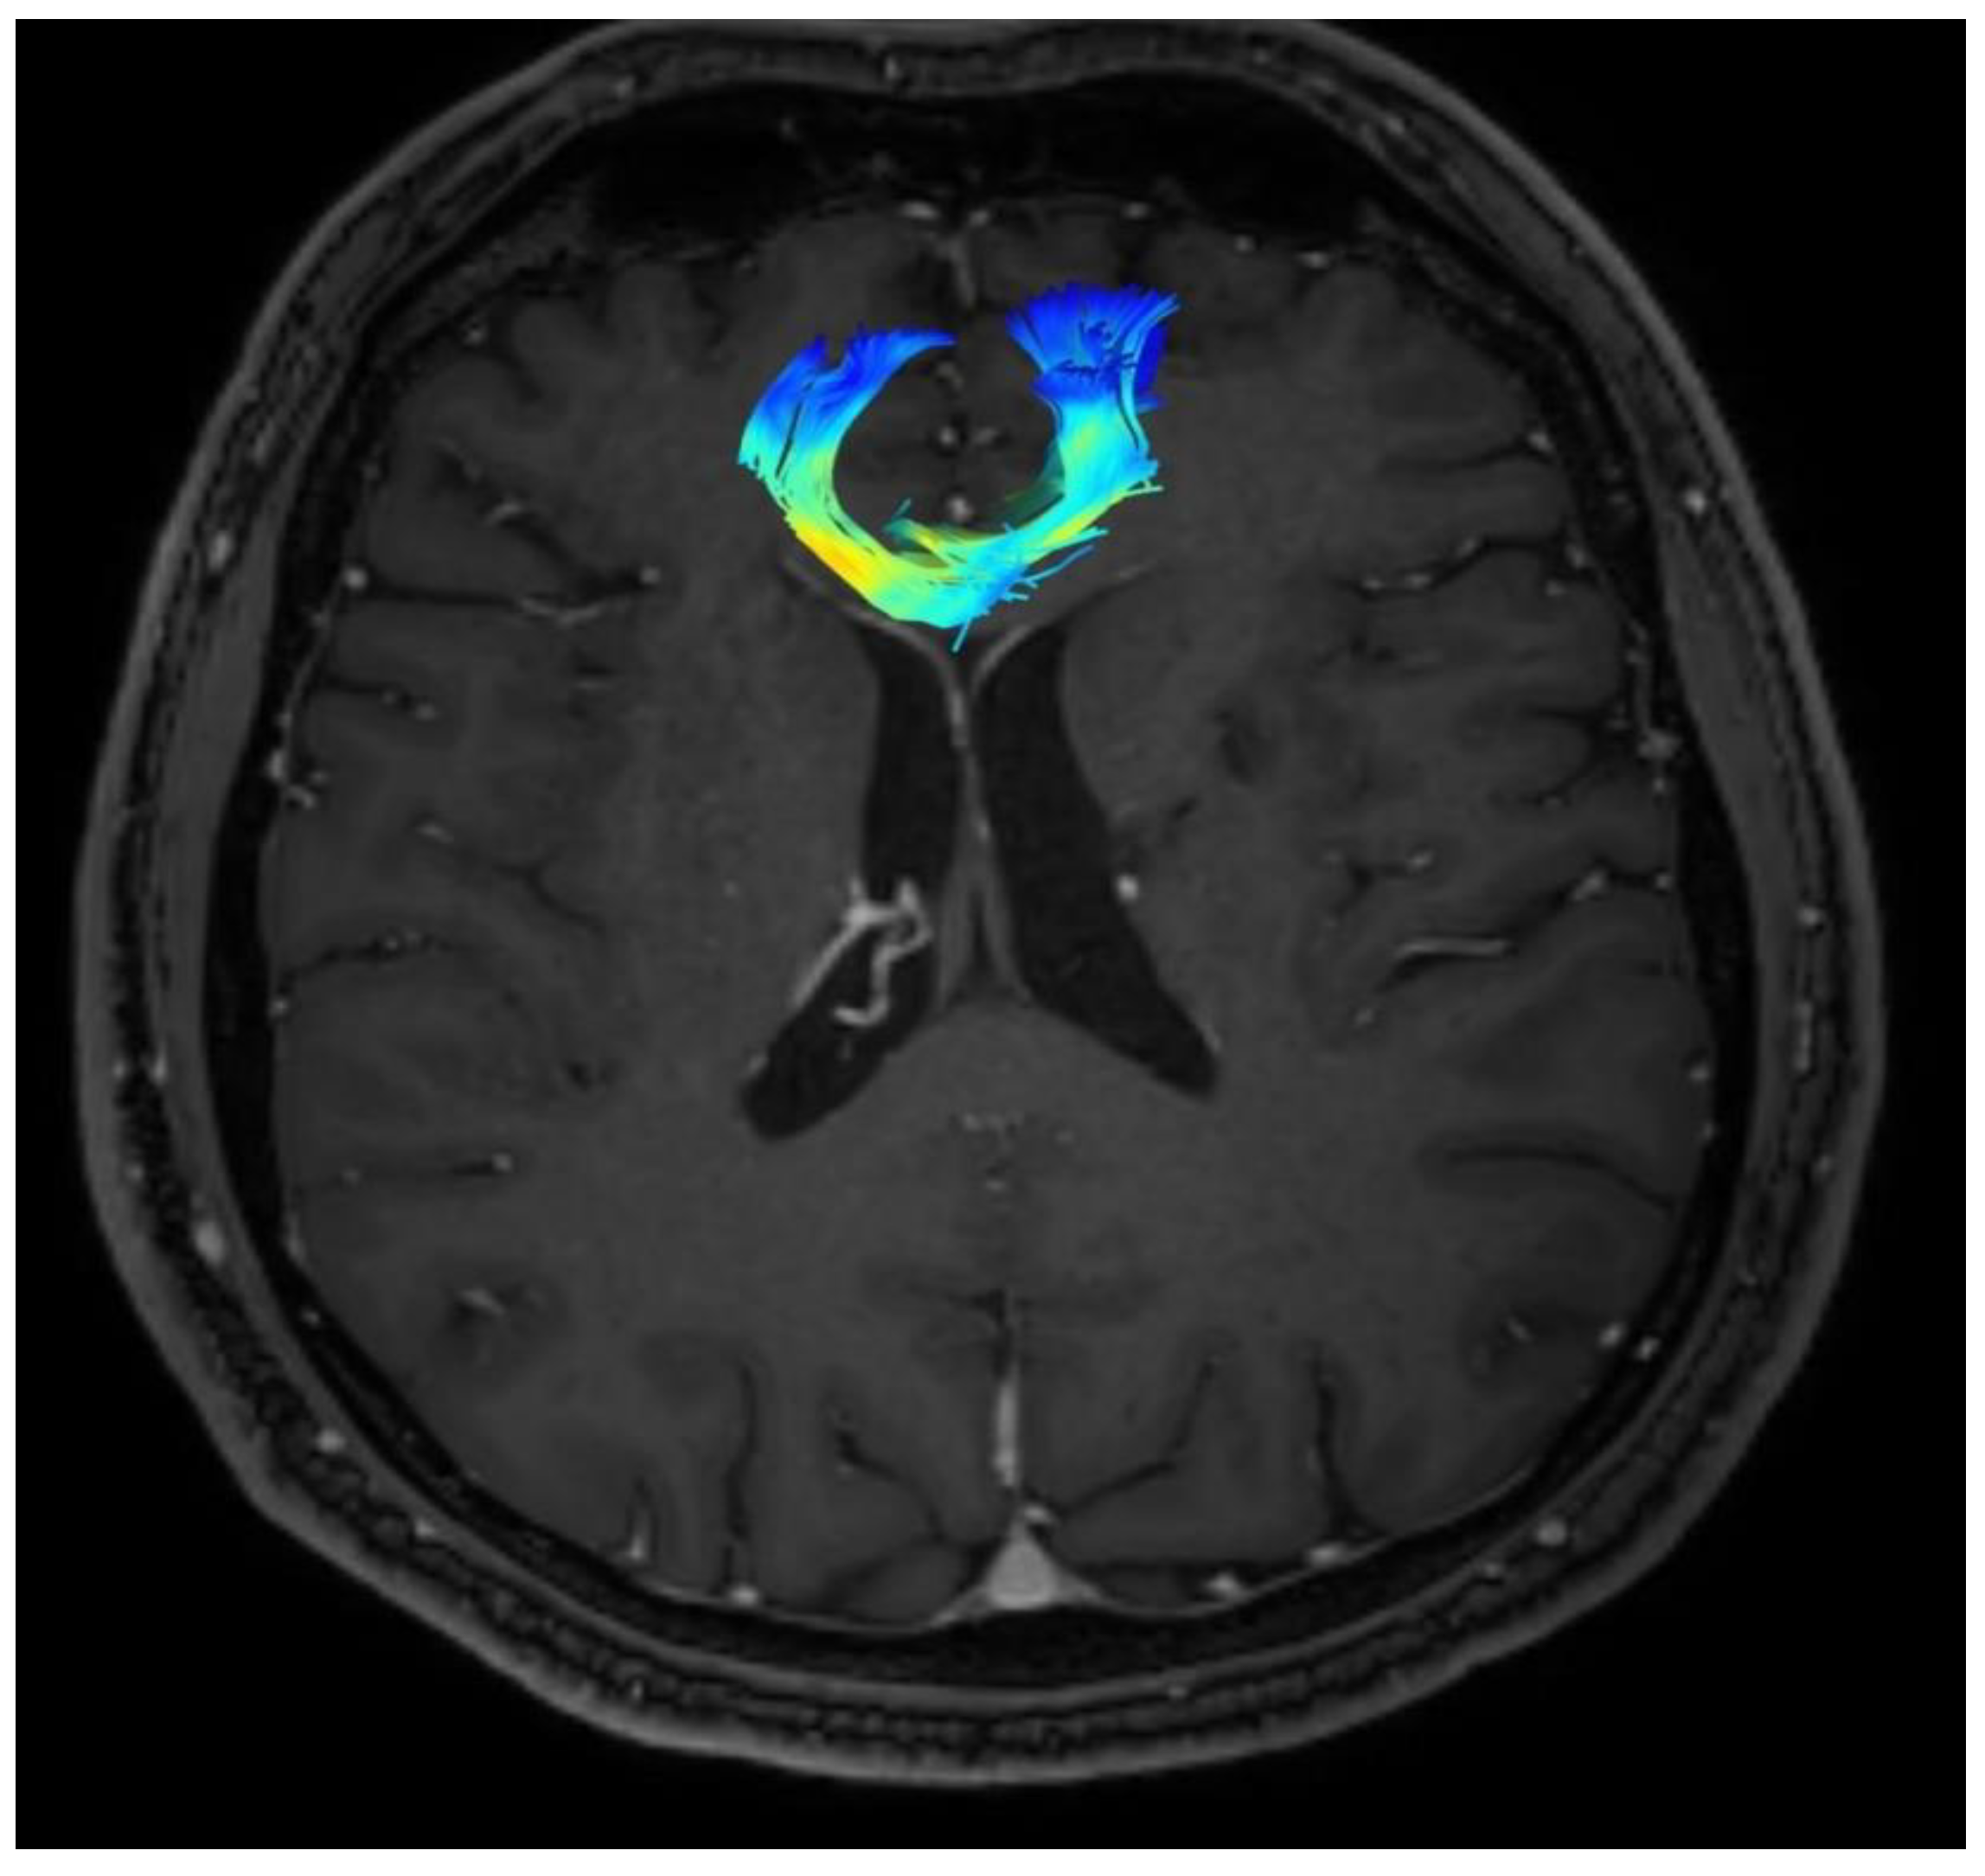

A planning of cingulotomy procedure is presented in Figure 1.

Figure 1. Planning of cingulotomy procedure.